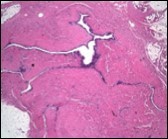

Figure 5.Cutaneous ciliated cyst with incomplete intervening septa and a lining of attenuated, ciliated epithelium along with supporting fibrous tissue (13).

Figure 6.Cutaneous ciliated cyst with a ciliated cuboidal lining, undulations within the cyst cavity and a wall comprised of fibro-connective tissue (14).

Typically, cutaneous ciliated cyst is a simple cyst which demonstrates a layering of pseudostratified ciliated columnar epithelium recapitulating conventional epithelial lining of the fallopian tube. As the cutaneous ciliated cyst demonstrates a morphological similarity to the fallopian tube lining epithelium, a Mullerian origin is indicated. Gross examination of cutaneous ciliated cyst depicts a solitary, mobile, non-tender, fluctuant, firm or soft to cystic lump with a fibrous wall and abundant amount of circumscribing adipose tissue. Cutaneous ciliated cysts are of a variable dimension. Cut surface usually displays a unilocular cyst impacted with clear, serous fluid, an attenuated smooth, greyish/ white cyst wall incorporated with incomplete septa traversing the cyst 6, 7.

Cutaneous ciliated cyst is layered with a singular layer of ciliated epithelial cells which are chiefly constituted by cuboidal to columnar epithelium, traversed by partially configured fibrous tissue septa with an admixture of randomly dispersed, intraluminal papillary projections akin to those cogitated in the fallopian tube. Superimposed epithelium is inundated with well vascularized, parallel bundles of collagen although smooth muscle is absent 7, 8.